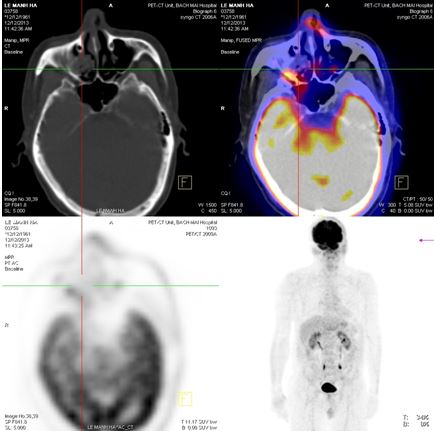

+ Tháng 12 năm 2013, bệnh nhân được chup PET/CT lần 2 sau khi kết thúc xạ trị và 4 đợt hoá trị. Trên hình ảnh PET/CT cho thấy: vùng đáy lưỡi có khối tăng hấp thu F-18 FDG, kích thước 3,9x4,3x3,0cm, theo dõi tổn thương viêm sau xạ trị. Không thấy hạch cổ tăng hấp thu F-18 FDG bất thường.

Hình 6. Hình ảnh PET/CT sau xạ trị 70Gy và 4 đợt hoá trị